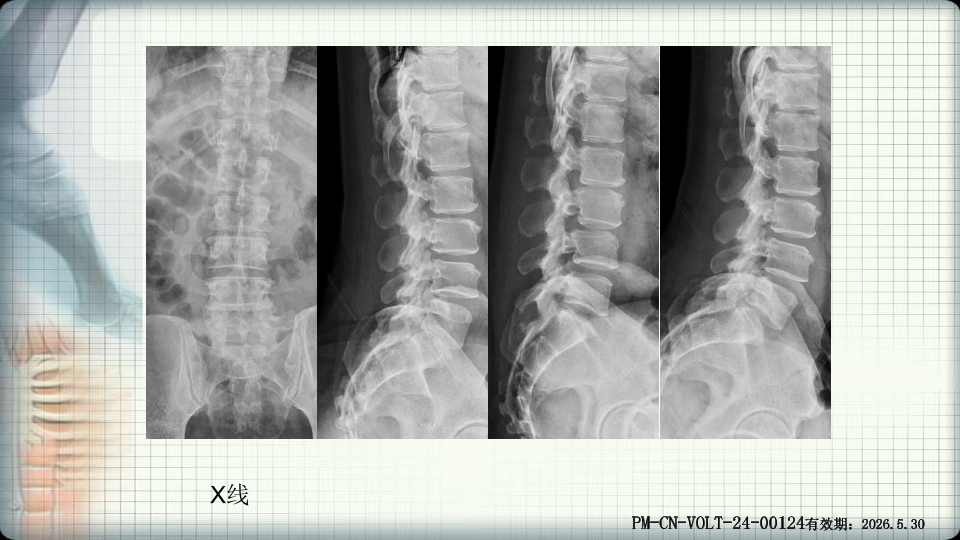

管狭窄症非手术治疗-谢学虎